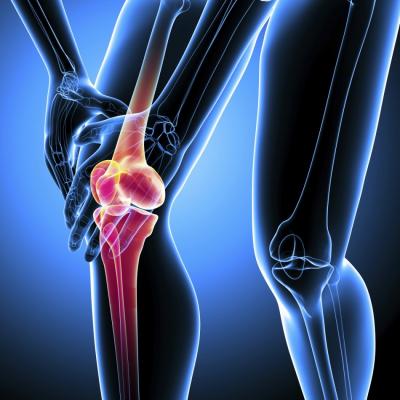

जॉइंट आपल्या शरीराचा असा भाग आहे जिथे दोन किंवा त्यापेक्षा अधिक हाडे एकमेकांना मिळतात. जसं की, कंबरेच्या हाडाचं असतं. इथे मांडीच्या हाडाचा वरचा भाग पेल्विसच्या सॉकेटमध्ये फिट असतो. जॉइंटमधील हाडे एक लवचिक पण मजबूत कार्टिलेजने कव्हर असतात. त्यामुळे ही हाडे एकमेकांना न घासता मुव्ह करतात.

ऑस्टिओआर्थरायटिस जॉइंटमधील हाडांवरील कार्टिलेजचा हा थर कमजोर करतं. त्यामुळे आपल्या जॉइंटचा सरफेस रफ होतो. याकारणाने जॉइंटममध्ये सूज, वेदना आणि ताण निर्माण होतो. पण ही लक्षणे प्रत्येक व्यक्तीत दिसत नाहीत.

जॉइंटमध्ये ताण जास्तकरून सकाळच्या वेळी किंवा इनॅक्टिविटी पिरिअडनंतर ऑस्टिओआर्थरायटिसची वॉर्निंग साइन असू शकते.